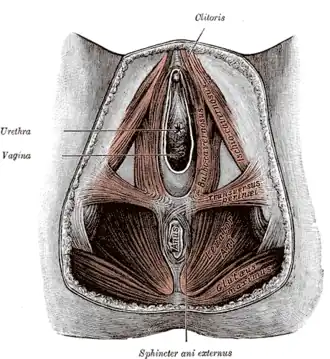

Промежность условно делят на два отдела, границей между которыми служит линия, соединяющая седалищные бугры. Передний отдел получил название мочеполовой диафрагмы, а задний — диафрагмы таза.

Через мочеполовую диафрагму у мужчин проходит только мочеиспускательный канал, а у женщин помимо него ещё и влагалище. Основу мочеполовой диафрагмы составляет глубокая поперечная мышца промежности. Эта мышца, расположенная между костями лобковой дуги, с обеих сторон покрыта фасцией, волокна мышцы имеют преимущественно поперечное направление. Часть мышечных волокон в том месте, где через мочеполовую диафрагму проходит мочеиспускательный канал, приобретают круговое направление и именуются наружным сфинктером мочеиспускательного канала (произвольным). У женщин волокна сфинктера мочеиспускательного канала охватывают также влагалище, оканчиваясь позади него в сухожильном центре промежности.

В области мочеполовой диафрагмы различают ещё мышцы, связанные с пещеристым и губчатым телом.

Через диафрагму таза проходит конечный участок прямой кишки. Здесь расположен наружный сфинктер заднего прохода. Наиболее крупной мышцей диафрагмы таза является мышца, поднимающая задний проход. Она начинается от стенок малого таза и, направляясь назад и книзу, охватывает прямую кишку, вплетаясь в наружный сфинктер заднего прохода. Эта мышца напоминает воронку, которая суживается книзу. Снаружи и изнутри она покрыта фасциями. Её функция заключается преимущественно в удержании внутренних органов, расположенных в малом тазу.